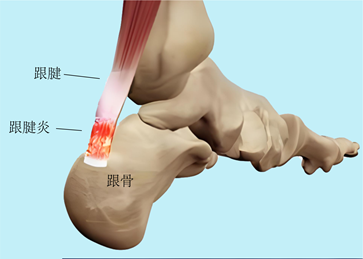

(三)跟腱炎

跟腱炎是由于跟腱反复受到剧烈拉伸产生劳损后引起的退行性病变,主要表现为跟后部疼痛、肿胀和僵化,活动后加重。

青少年跟腱炎发病率不高,多认为是运动过量引起的,也可能与劳损、外伤、感染等原因有关,应根据病因进行治疗。

▶跟腱炎分为止点性和非止点性跟腱炎,儿童以止点性跟腱炎多见。

▶治疗应先选择保守治疗,包括合理休息、辅具治疗、物理治疗和康复治疗。

图9:跟腱炎